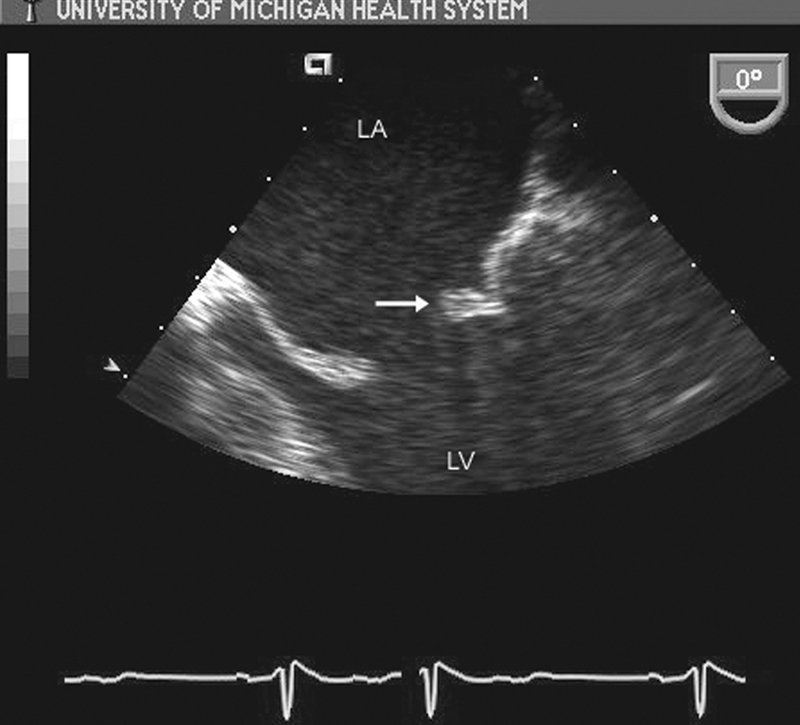

فحوصات تشخيصية لبعض امراض القلب والشرايين التاجية